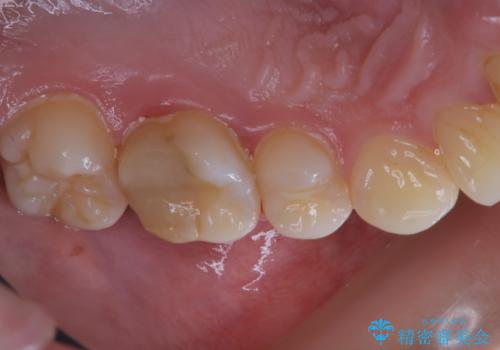

治療の前にPMTCできれいでツルツルな歯に

- 今後治療を進めていく予定で、まずはきれいにクリーニンングから行いたいとのことでした。PMTC60分コースを行いました。

PMTCを行う際には担当の歯科衛生士が、患者様1人1人の虫歯・歯周病などのリスク・ブラッシングスキルなどを確認します。

単なる磨き方の指導だけではなく、歯並びや歯肉の状態、ライフスタイルなどにより、患者様に適した歯ブラシや歯磨剤の選択をしたり、お口のお悩みについてのご相談も承っております。

定期的にPMTCでメンテナンスを行うことで、なにかあった時の早期発見につながります。

日々の磨き残しや唾液の成分などによりバイオフィルムや歯石はどうしても付着してしまいます。歯石や汚れを放置していると、そこで病原菌が繁殖す始めます。歯肉に炎症が生じると歯周病などの引き金となります。

そのため、2~3か月に1回は、歯科医院での専門的クリーニングをすることが大切です。